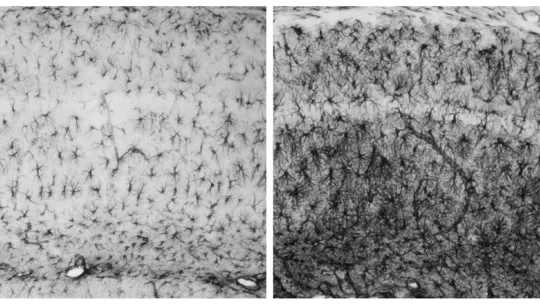

Guinovart y su equipo, especialistas en el metabolismo del glucógeno, demostraron en 2007 en un artículo en Nature Neuroscience que mutaciones en cualquiera de estos dos genes provocan la acumulación de glucógeno –cadenas de azúcar- en las neuronas, lo que les es tóxico y precipita su muerte celular. Asimismo, demostraron en ratones que bloqueando la síntesis de glucógeno en las neuronas, la enfermedad no se desencadena, identificando así un posible tratamiento para Lafora.

In an article published in Nature Neuroscience in 2007, Guinovart and the members of his team, experts in glycogen metabolism, demonstrated that mutations in either of these two genes lead to the accumulation of glycogen—chains of sugar—in neurons, thus causing toxicity and triggering neuronal death. Likewise, using mice, they showed that the inhibition of glycogen synthesis in neurons prevents the development of Lafora disease, thereby identifying a possible treatment for this condition.